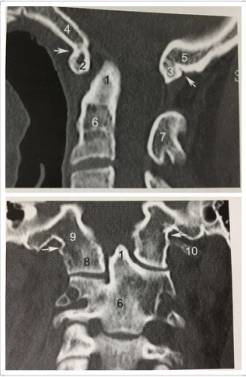

12、齿状突终末小骨

终末小骨位于齿状突尖部“V”形裂隙内,易误认为是碎骨片。

13、寰椎后弓旁正中央裂

寰椎后弓旁中央裂为正常变异,易误为骨折。

14、寰椎同化

寰椎前弓(2)与枕骨斜坡(4)、后弓与枕骨大孔后缘(5)、侧块(8)与枕骨髁融合。1、齿状突。6、枢椎椎体。7、枢椎棘突。10、寰椎横突。